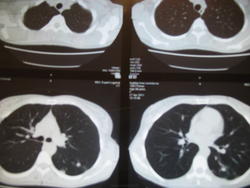

40 лет, жен, ВДТБ-МЛУТБ (S6 инф.) лечение окончено, рассасывание и уплотнение, но по состоянию и по общим и биохимическим анализам сильная интоксикация. Прошу посмотреть (КТ сдкланы без контраста). Возможно, поможите найти причины интоксикации или посоветуете другие дообследования (КТ уже боюсь - было 8 за 2 года + множество снимков и томограмм). Возможно, какой то намек на лимфааденит?

Сделаны: 04,11

Сделаны 08,11:

ВДТБ-МЛУТБ - что это? Если это туберкулез, то туберкулеза (на мой взгляд) у Вас нет. Диф. диагноз изменений в S6 слева - между COP и ТЭЛА мелких ветвей (раз уж Вы так любите аббревиатуры)...

Извините за аббревиатуру,я думала ее все врачи знают.Это вперые диагностированый туберкулез,который оказался мультирезистентным(по посевам).Прошу посмотреть динамику,мои врачи ничего не видят,что вызывало бы интоксикацию,предлагают сделать КТ с контрастом для

Т.е. на последнем КТ динамика к ухудшению?Я лечилась почти 2 года без перерыва,фтизиатры на данный момент не видят причин по КТ придолжать или изменять лечение,по спец. анализам(посевы) -тоже.Но видя интоксикацию,считают одних клинических проявлений не достаточно для лечения(по большому счету им всеравно,лишь бы я никого не заражала).Поэтому я и обратилась к вам для изучения динамики.Гематолог и терапевт направляют меня к фтизиатру,а фтизиатры...(КТ на снимках за 2011 год,а на дисках за 2012,2013,остальные не выкладывала,т к они только дублируют информацию,потому что были сделаны через очень короткие промежутки времени.Спасибо.